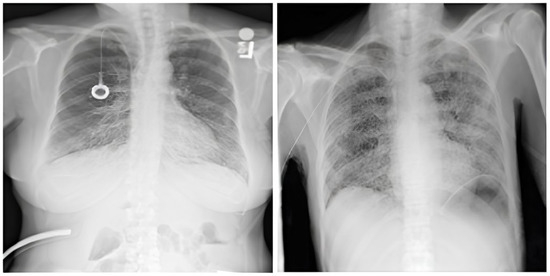

The dataset comprises 112,120 X-ray images with disease labels from 30,805 unique patients [21]. The samples from the CXR NIH dataset are shown in Figure 3. Disease labels were extracted from radiology reports using NLP, achieving over 90% accuracy and supporting weakly supervised learning.

Figure 3.

CXR NIH dataset samples [21].

3.1.2. CheXpert Dataset

This is an extensive and meticulously curated collection comprising 224,316 chest radiographs obtained from 65,240 patients who underwent radiographic examinations at Stanford Health Care facilities over a substantial timeframe spanning from October 2002 to July 2017 [24,25]. The samples from the CheXpert dataset are shown in Figure 4. These examinations were performed across a diverse range of settings, including inpatient and outpatient centers, ensuring the inclusion of a broad spectrum of clinical scenarios and patient demographics. Each radiograph in this dataset has been labeled for 14 distinct, standard chest radiographic observations, aligning with established clinical guidelines and fostering consistency in labeling across the dataset.

Figure 4.

CheXpert dataset samples [24].